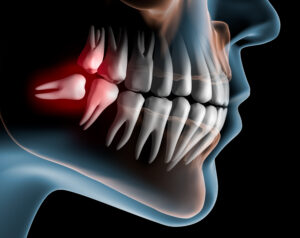

When people have impacted wisdom teeth, they can experience several problems – including intense dental pain, swollen and tender gums, and discomfort. There are numerous

When people have impacted wisdom teeth, several problems can occur. Impacted wisdom teeth cause problems like intense pain, swollen and tender gums, and discomfort. For

Dealing with impacted wisdom teeth can be a very painful experience. When people have wisdom tooth removals, it can alleviate the symptoms of impacted wisdom

Patients can have a painless and anxiety free wisdom tooth removal in Greensburg, PA when they are given sedation dentistry and are treated with the